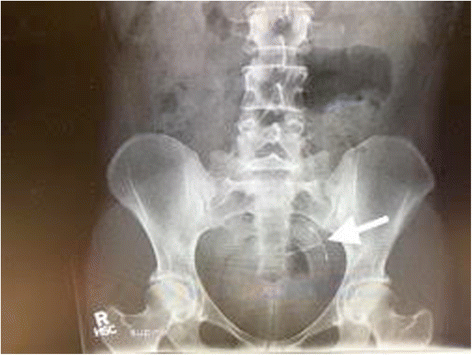

A 30-year-old white woman, gravida 1, para 1, presented to our hospital for scheduled laparoscopy after IUD threads were not visualized on speculum examination during a 6-week placement check. The hormonal IUD had been placed 8 weeks after an uncomplicated cesarean delivery and our patient was concurrently breastfeeding. Pelvic ultrasonography did not show intrauterine placement of the IUD. Subsequent abdominal radiography located the IUD in the left anterior aspect of her pelvis (Fig. 1).